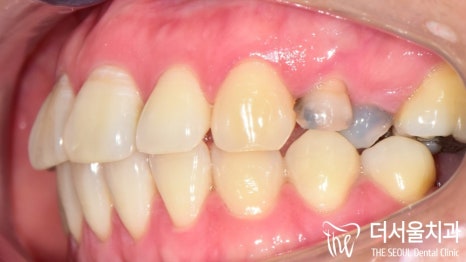

장치를 부착하여 견인을 하고 있는 모습입니다.

이후 치열 정돈 및 교합, 컨택 등을 맞춰가며

클린체크에서 확인했던 모습처럼

개선을 도와드릴 예정입니다 🙂